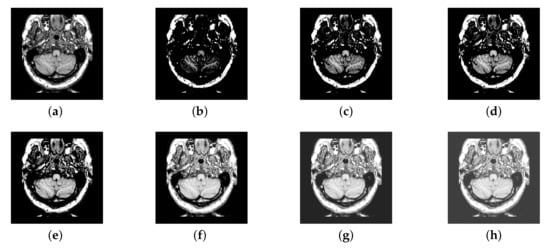

In previous intuitionistic fuzzy sets, scholars usually set to the order of 10 squares. Here, we set to 200, 300, 400, 500, 600, 700, and 800, respectively. Then, the image enhancement experiment is carried out, and the experimental results are shown in Figure 6. According to the results, we can find that, when is set to 500, the result is better than others.

Figure 6.

Source image and its image reconstructed by different algorithms): (a) Source image, (b) = 200, (c) = 300, (d) = 400, (e) = 500, (f) = 600, and (g) = 700, (h) = 800.